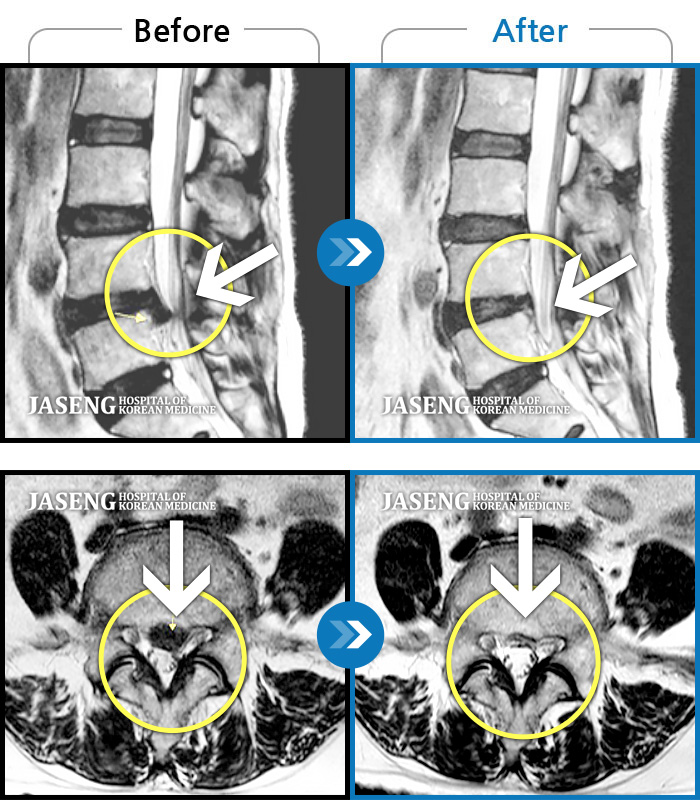

Before

After

환자에게 사전 동의를 받아 동일 조건에서 촬영되었습니다.

개인에 따라 치료 후 부작용이 발생할 수 있으니 의료진과 상담 후 치료를 진행하시기 바랍니다.

허리에서 다리까지 통증

허리 우측에서 발바닥까지 통증, 누워있을 때 당기는 증상